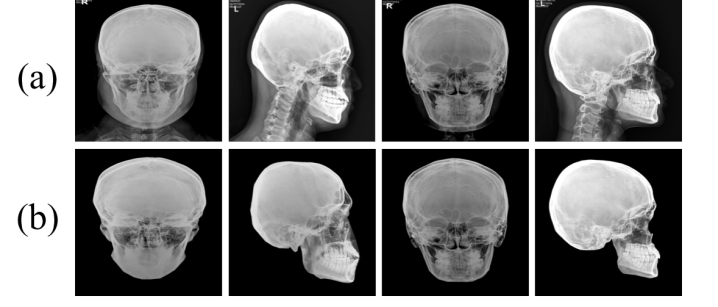

Figure 3: Sample soft tissue eliminated X-ray images in frontal and lateral views, respectively, where (a) is the real X-ray images and (b) is the soft tissue eliminated images.

As mentioned in Section §3, we have 2D X-ray images of faces that resemble skull images. However, the X-ray images also contain the effect of soft tissue. To ensure that the X-ray images accurately represent the skull, we manually removed the soft tissue components from the 2D X-ray images. Figure 3 shows some samples of real and soft tissue eliminated X-ray images, respectively.